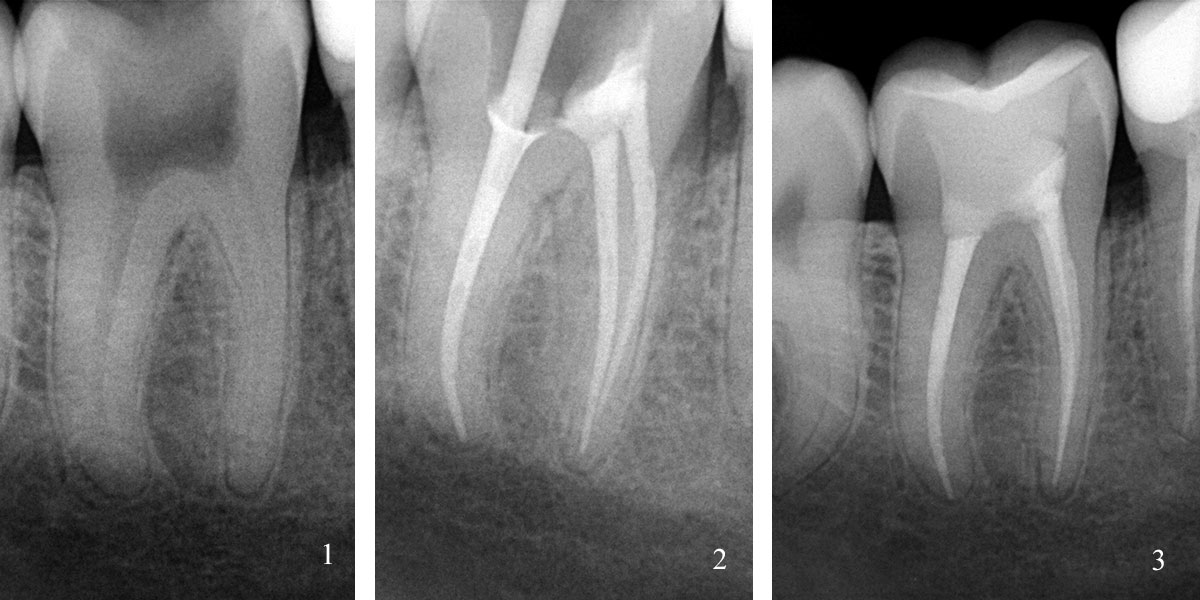

Также на всех этапах лечения зуба мы проводим контроль на высокоточном современном визиографе PLANMECA ProX и Dr.Suny с избирательной дозой облучения, благодаря чему лучевая нагрузка на пациента сводится к минимуму.

С помощью рентгена врач может увидеть состояние каждого зуба и его корней, рядом расположенные органы и ткани. Процедура помогает поставить правильный диагноз перед началом лечения и позволяет оценить качество работы стоматолога во время лечения и после его окончания, что очень важно при пломбировании каналов, удалении зубов, установке имплантатов.